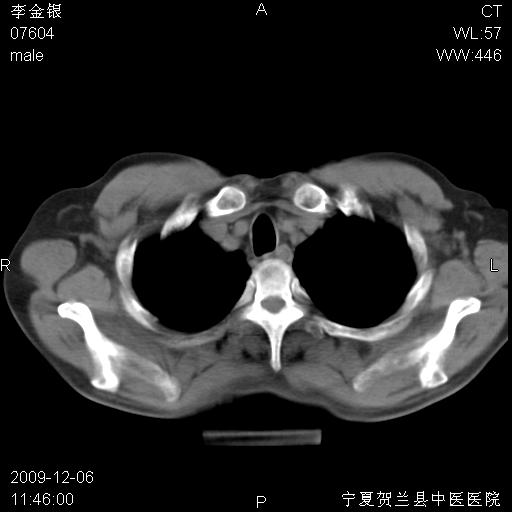

该病人 ,男,62岁,主因咳痰带血两天

支气管鼠尾状狭窄应该是肿瘤

支气管壁明显增厚 管腔狭窄,腔静脉后多个淋巴肿大,结合年龄病史考虑右肺上叶中央型肺癌并阻塞性肺炎

右上叶支气管狭窄,管壁增厚,远端斑片状软组织影,病灶邻近叶间裂,叶间裂无移位。

诊断右肺中央型肺癌。

那个片影应该大部分都是病灶,病灶沿肺段支气管分支生长,后段完全显示不清、闭塞。若为不张应该伴有叶裂的移位,若为炎症应有空气支气管征。